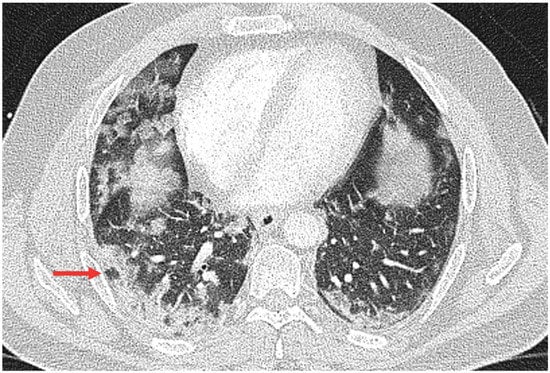

3.2. Qualitative Scoring, Pattern Distribution, Morphology, and Virus Variant

3.3. Semiquantitative Scoring and Virus Variant

3.4. Inter- and Intrareader Variability